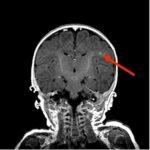

Infant tuberculosis (TB) is a rare but potentially deadly infection and difficult to diagnose, especially in infants who may present with non-specific symptoms. Here, we report a case of an United States-born term infant with community-acquired miliary TB and no confirmed TB exposure history. The patient initially presented with respiratory distress at seven weeks of life with chest radiograph showing a right lower lobe (RLL) infiltrate. After failing multiple courses of treatment for community-acquired pneumonia and developing growth faltering, the patient had imaging findings suggestive of TB infection with CNS involvement. The diagnosis of TB was confirmed by QuantiFERON and purified protein derivative (PPD). In infants who fail conventional treatment for bacterial pneumonia, the differential should be broadened to consider alternative etiologies. Additionally, brain imaging should be performed in cases of disseminated TB despite negative cerebrospinal fluid (CSF) studies since these patients are at high risk of central nervous system (CNS) involvement.